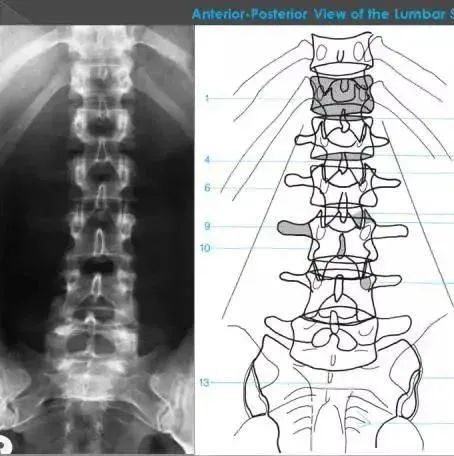

X线入门 | 详细的腰椎X线解剖+解读

腰椎的X线解剖

医学界骨科频道 2020-08-26